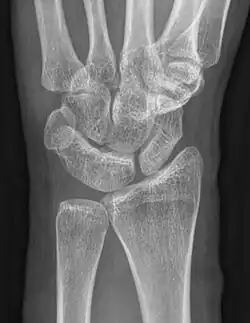

Eine karpale Koalition ist eine feste Verbindung zwischen Handwurzelknochen, die normalerweise über ein Gelenk in Kontakt stehen. Dabei kann diese Verbindung knöchern (Synostose), knorpelig (Synchondrose) oder bindegewebig (Syndesmose) ausgebildet sein. Als Ursache wird von einer mangelhaften Differenzierung der Handwurzelknochen zwischen der 4. und 8. Embryonalwoche ausgegangen[1].

Wenn eine karpale Koalition isoliert auftritt, was der häufigere Fall ist, sind in der Regel zwei Knochen der gleichen Handwurzelreihe betroffen, beim Auftreten im Rahmen von Syndromen oder anderen globaleren Störungen treten auch Verbindungen von mehreren Knochen beider Reihen auf[1][5]. Die bei Weitem am häufigsten verschmolzenen Knochen der Handwurzel sind Os lunatum und Os triquetrum gefolgt vom Os hamatum mit dem Os capitatum[1].